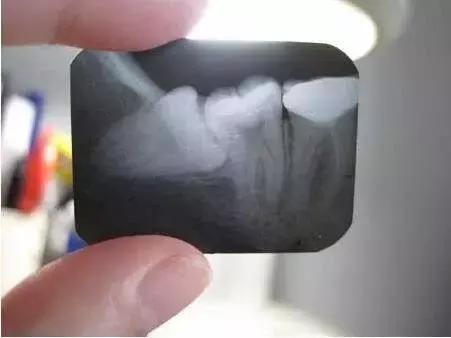

4、 会影响其他牙齿龋坏:阻生智齿能使第二磨牙龋坏。向前倾斜的智齿,其牙冠顶在前牙的颈部,这两颗牙之间形成一个滞留区,由于食物残渣的滞留,得不到正常清洁,细菌繁殖产酸,腐蚀牙齿,造成第二磨牙牙颈容易发生龋齿,往往就诊时已不能保留,需要拔除。